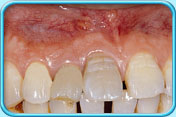

牙齒表面有啡黃或白斑

治療方法

初期蛀牙

牙科醫生可於牙齒表面塗上牙面氟化物劑,使初期蛀牙得以修復

牙齒發育時受感染或氟斑牙

以複合樹脂補牙、做貼面修復治療或鑲配人造牙冠

填上複合樹脂後的牙齒